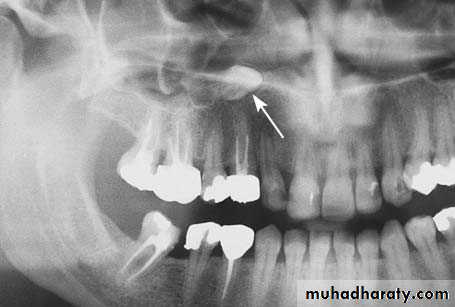

Radiograph showing impacted canine with a labial localization, which is in contact with the anterior wall of the maxillary sinus

Incision in canine fossa region, for sinus trephination using the Caldwell–Luc approach

Reflection of the mucoperiosteal flap and exposure of the anterior wall of maxillary sinusFirst a horizontal incision is made in the region of the canine fossa, from the lateral incisor as far as the first molar.

The mucoperiosteum is then reflected and the bone of the anterior wall of the maxillary sinus is exposed.

Holes are drilled through the bone using a small round bur where the impacted tooth is estimated to be, and these holes are then joined together. After removal of the bone surface, the impacted tooth is exposed and carefully luxated outwards.

Holes drilled through the bone surface defining the border of bone to be removed

Connecting holes to remove the bone covering the impacted tooth.